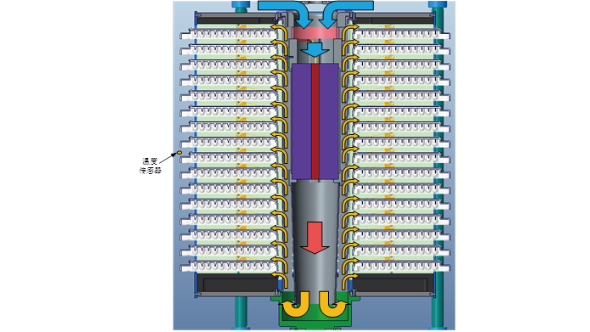

Accurate

- • Multi-wavelength detection: A five-wavelength detection system is adopted to accurately match the characteristic wavelengths of different biochemical chromogenic reactions to obtain more specific interpretation data and improve the accuracy of results;

- • Dynamic detection: The intelligent dynamic recognition algorithm is used to perform cyclic dynamic (20min) interpretation of the test card, which not only improves the accuracy of the results, but also improves the timeliness of the detection. The results can be produced in 4 to 5 hours at the fastest, which greatly shortens the TAT.